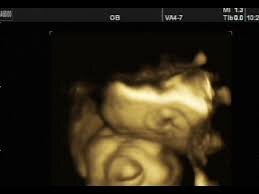

Вот так эта аномалия выглядит на УЗИ

анэнцефал — ребенок с тяжелой аномалией развития в виде отсутствия головного мозга. Патология эта несовместима с жизнью, даже если ребенок родился живым, он умрет в первые сутки-двое, а вероятнее, в первые часы или минуты. Аномалию эту умеют хорошо диагностировать — слава УЗИ-скринингам.